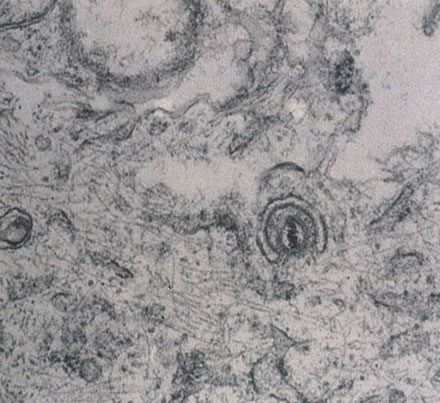

Any cell type may be infected, appearing larger than normal (cytomegalic) and demonstrating eosinophilic intranuclear “owl's eye” and smaller intracytoplasmic viral inclusion bodies, which are better seen with Giemsa or Papanicolaou's stains (Fig. 8). Histologic examination of tissue specimens, including bronchoalveolar lavage fluid and urine, may be useful for diagnosis.

Fig. 8. Typical lesion of cytomegalovirus (CMV) produces retinal necrosis with large cells possessing owl's eye inclusions.